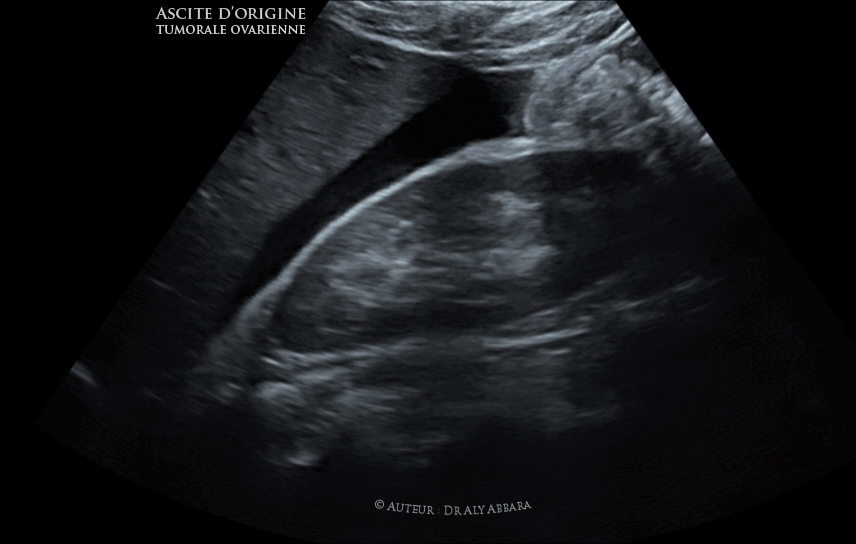

Ascite péritonéale d'origine tumorale ovarienne

Séquences Vidéo et images échographiques mettant en évidence une ascite péritonéale d'origine tumorale ovarienne :

L'espace de Morisson (ou l'espace interhépatorénal droit) est occupé par une large lame d'ascite ainsi le cul de sac postérieur avec également les anses grêles baignant dans ce liquide d'ascite.

L'ascite (ou l'épanchement d'un liquide séreux dans la cavité péritonéale) chez cette patiente de 32 ans est associée à la présence d'une tumeur ovarienne bilatérale de type de cystadénome ovarien bilatéral papillaire séreux à la limite de la maliginité (borderline).